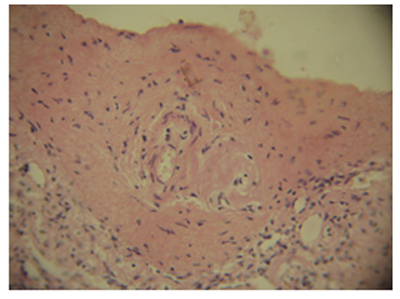

ՊՀ պայմանավորված լյարդի ախտահարումը դրսևորվել է ամիլոիդի առկայությամբ լյարդի դրունքային ուղիներում` անոթների, հատկապես զարկերակների և զարկերակիկների պատերում (նկ. 2): Ներբլթակային հենքում ամիլոիդոզն արտահայտված չէր:

Նկ. 2. Ամիլոիդային կուտակումներ լյարդի դրունքային զարկերակի պատում,հեմատոքսիլին- էոզին, x400 |